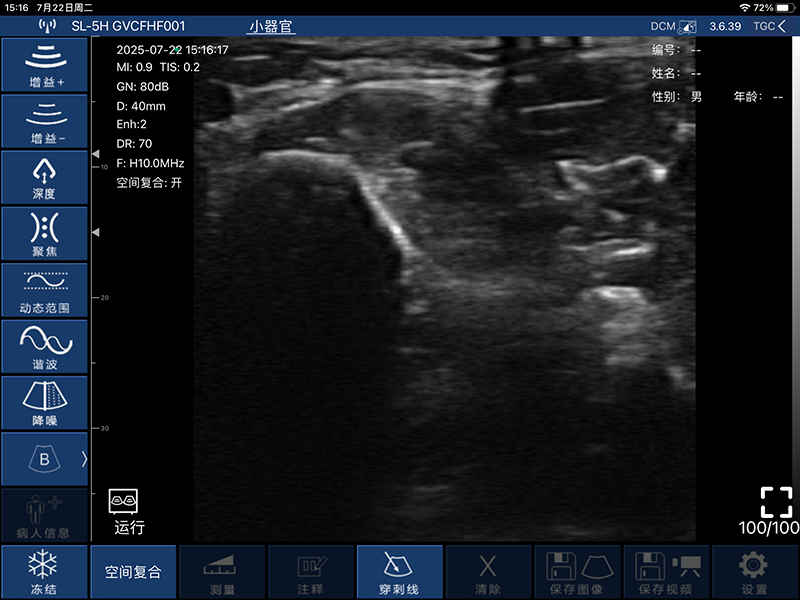

带指套探头的掌上彩超,小小的掌超主机放在口袋可随处走,手指套着探头即可完成打图成像,让手不再需要握着探头而可解放出来还能拿其他东西,特别适合术中等应用

- 穿刺辅助功能:平面内穿刺引导线功能,平面外穿刺引导与血管自动测量功能

- 测量功能:距离、面积、周长、心率、产科

- 电影回放:手动和自动回放,可设置回放帧数为100/200/500/1000

- 图像保存:jpg, mp4, png, DCM多种格式